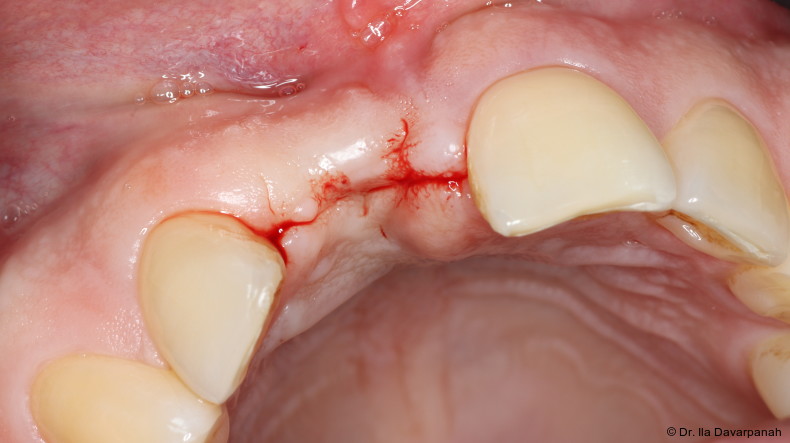

Nach Entfernung des frakturierten Implantatkörpers erfolgte eine erneute Sofortimplantation mit einem alternativen Implantatdesign. Begleitend wurden Maßnahmen zur Stabilisierung von Hart- und Weichgewebe durchgeführt.

Die postoperativen Verlaufskontrollen zeigten stabile periimplantäre Verhältnisse ohne weitere Komplikationen. Die Osseointegration sowie die Weichgewebesituation stellten sich unauffällig dar.